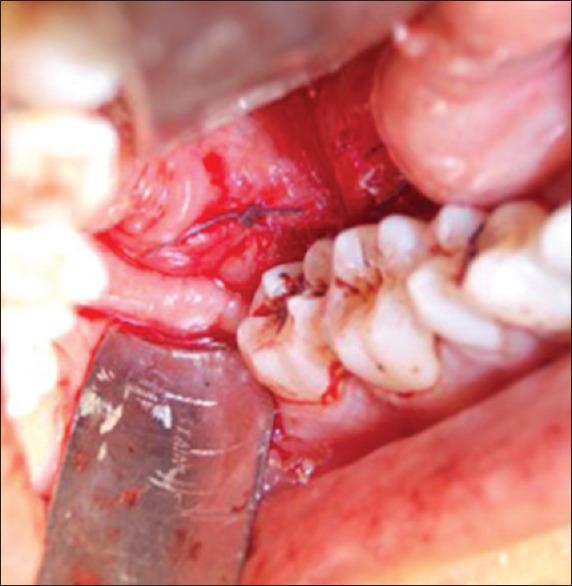

Iatrogenic displacement of a tooth or tooth fragment is a rare but well-recognized complication that occurs during exodontia. The most common sites of dislodgment of a mandibular third molar fragment are the sublingual, submandibular, and pterygomandibular and lateral pharyngeal spaces. Removal of a displaced tooth from these spaces may be complex due to poor visualization and limited access. A thorough evaluation of all significant risk factors along with precise localization of the tooth by clinical and radiographic means should be performed to prevent untoward complications. This paper reports two cases of iatrogenic displacement of mandibular third molar teeth, in the sublingual space and lingual pouch. Both the cases were managed intraorally under general anesthesia, and the postoperative healing was satisfactory and uncomplicated. A brief review of literature is also provided in this paper.

摘要

牙齿或牙碎片的医源性移位是拔牙过程中一种罕见但已被充分认识的并发症。下颌第三磨牙碎片最常见的移位部位是舌下、颌下、翼下颌和咽旁间隙。由于视野不佳和操作空间有限,从这些间隙取出移位的牙齿可能很复杂。应通过临床和影像学手段对所有重要危险因素进行全面评估,并精确确定牙齿位置,以预防不良并发症。本文报告了两例下颌第三磨牙医源性移位至舌下间隙和舌袋的病例。两例均在全身麻醉下经口处理,术后愈合良好,未出现并发症。本文还对相关文献进行了简要综述。